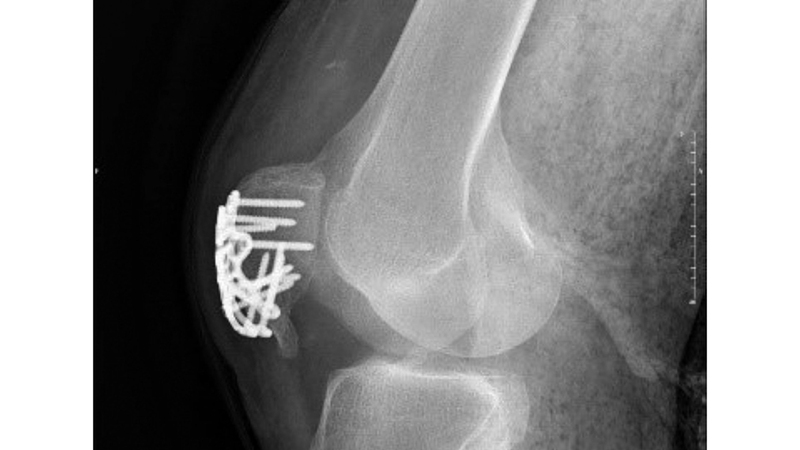

وقال إن الفريق الطبي في المستشفى استفاد من تقنية مبتكرة تُعدّ الأولى من نوعها في الإمارات، تمثّلت في استخدام صفيحة خاصة تتيح قفل البراغي، ما يوفر تثبيتاً آمناً للعظام المكسورة، لاسيما في حالات هشاشة العظام.